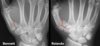

**Colles - ‘dinner fork type deformity’** Features of the injury 1. Transverse fracture of the radius 2. 1 inch proximal to the radio-carpal joint 3. Dorsal displacement and angulation of the distal radius

34

Colles vs Smith fracture

Colles fracture ## Footnote Typically FOOSH forwards Extra-articular radial # with dorsal (posterior / back of hand) angulation and displacement

Smith Fracture ## Footnote Typically FOOSH back of hand Extra-articular radial # with volar (anterior / palmar) angulation and displacement